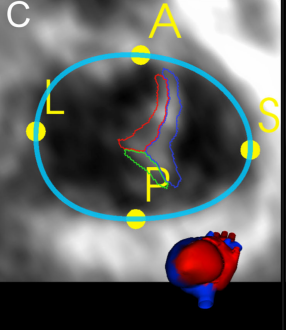

- Valve quadrant landmarks corresponding to APSL (Anterior, Posterior, Septal, Lateral) regions of the annulus are identified

The Annular Curve with quadrant landmarks